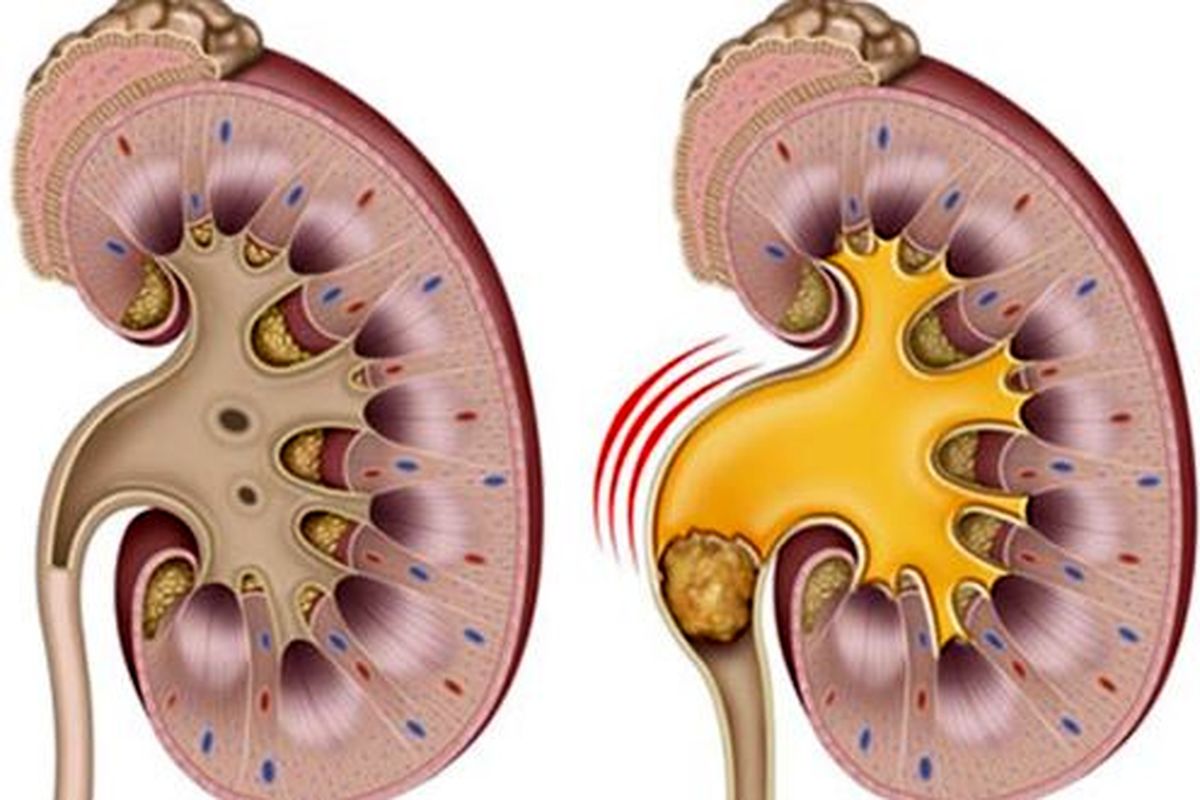

اگر میخواهید از تشکیل این سنگها پیشگیری کنید، باید از علل ابتلا به این سنگها آگاه باشید.

احتمال ابتلا به سنگ کلیه به دلیل عواملی مثل کاهش مایعات بدن در ماههای گرم تابستان افزایش مییابد.

آنچه افراد میخورند و می نوشند به طور مستقیم با خطر ابتلاء به سنگ کلیه در ارتباط است.

قهوه و دیگر نوشیدنیهای کافئین دار تأثیر زیادی در کاهش احتمال ابتلاء به سنگ کلیه دارند.